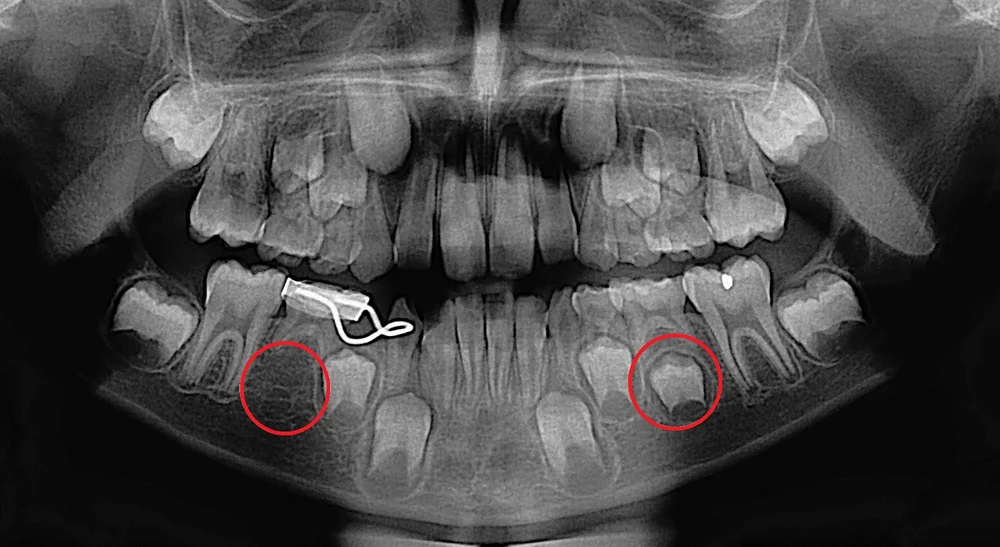

Panoramic X Ray Of Dentition In Case 1 The Deciduous Dentition Is Download Scientific Diagram

Panoramic Dental Xray Of Child Of Eight Years With The Problem Of Not Loosing His Baby Teeth Persistent Baby Teeth Stock Photo Download Image Now Istock